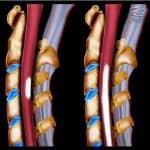

Viêm tuỷ cấp bao gồm những tổn thương cấp tính ở tuỷ sống, có thể tổn thương chất trắng hay chất xám của tuỷ sống hoặc toàn bộ ở một đoạn tuỷ hay vài đoạn kế cận nhau. Thuật ngữ chuyên biệt khác được sử dụng để chỉ ra chính xác hơn sự phân bố của quá trình viêm:

+ Tổn thương giới hạn ở chất xám là viêm tuỷ xám (poliomyelitis).

+ Tổn thương ở chất trắng là viêm tuỷ trắng (leucomyelitis).

+ Toàn bộ khu vực cắt ngang của tuỷ đều bị tổn thương được gọi là viêm tuỷ ngang (myelitis transversa)…